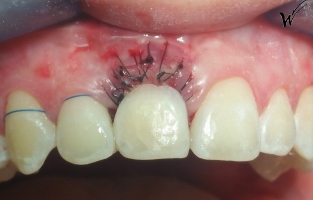

Afin de reconstruire l’os péri-implantaire et les tissus mous, une greffe épithélio-conjonctive a été réalisée pour restaurer le festonnage gingival et les papilles. La greffe pédiculée avec prélèvement palatin rétro-incisif permet de maintenir le volume gingival, conformément aux techniques de Zuhr et Hürzeler (2011) qui ont démontré l’efficacité des greffes tissulaires dans la restauration esthétique des papilles .

Le PRP (Plasma Riche en Plaquettes) et le PRF (Plasma Riche en Fibrine) ont été utilisés pour maximiser la régénération des tissus durs et mous. Selon une étude de Choukroun et al. (2006), le PRF stimule la cicatrisation et améliore la régénération des tissus péri-implantaires, en favorisant la revascularisation . Cette approche est essentielle pour garantir la cicatrisation primaire et prévenir la rétraction gingivale, comme le recommande également Misch (2015) dans les cas d’implantologie esthétique.